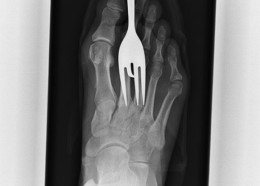

Чудни ренгенски снимки

Фото на денот #630